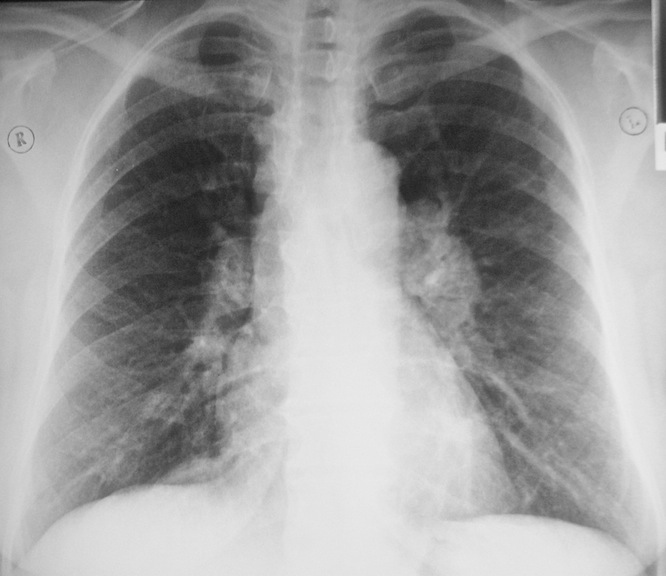

Саркоидоз легких - причины, симптомы, диагностика и лечение

Саркоидоз легких . Симптомы . Диагностика . Что делать при диагнозе саркоидоз легких . Консервативное лечение и операции . Платные и бесплатные клиники, в которых лечится саркоидоз легких .